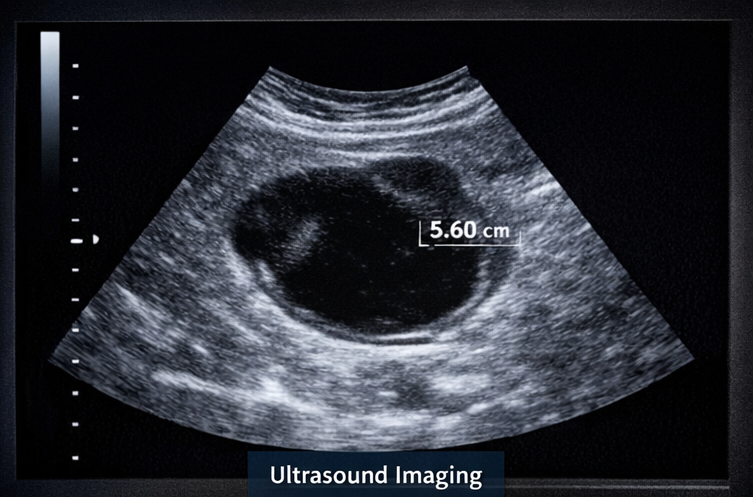

A 32-year-old female presented to the gynecology outpatient clinic with complaints of intermittent lower abdominal pain for the past two months. The pain was predominantly localized to the left lower abdomen, dull in nature, non-radiating, and occasionally associated with a sensation of pelvic heaviness. The patient also reported mild menstrual irregularity over the preceding three cycles, characterized by delayed menses.

Based on imaging findings, the cyst was provisionally diagnosed as a benign functional ovarian cyst.

At six-week follow-up, the patient reported significant reduction in abdominal discomfort and normalization of menstrual cycles. Repeat transvaginal ultrasonography demonstrated a marked reduction in cyst size to 2.3 cm.

At three-month follow-up, the cyst had completely resolved on imaging, and the patient remained asymptomatic. No adverse effects of treatment were reported. Continued routine gynecological follow-up was advised.